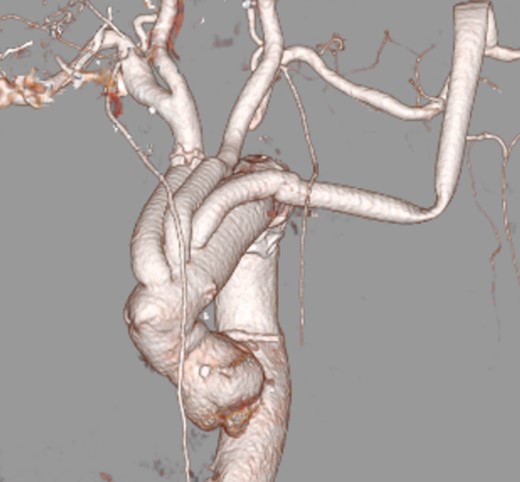

A 65-year-old woman admitted to a territorial hospital due to dizziness and listless feeling in the left arm. Magnetic resonance imaging revealed multiple CIs in the right frontal area and cerebellum on both sides (Fig. 1). Computed tomography angiography (CTA) detected stenosis in the IA and LSA (Fig. 2). No atrial fibrillation was detected despite repeated Holter-Electrocardiography. The patient was initially treated with aspirin, but thereafter experienced recurrent CIs. Clopidogrel was therefore added. Under double anti-platelet therapy, she suffered further CIs, and warfarin was added. However, CI occurred yet again. After six CIs, she was referred to our hospital.

After admission, carotid ultrasonography revealed a large, soft plaque with ulceration in the IA and a very mobile soft plaque in the LSA (Fig. 3). EVT was thus considered too dangerous, and TAR using a four-branched prosthesis was planned. Intraoperatively, bilateral axillary arteries were initially exposed, and an 8-mm vessel prosthesis was anastomosed. Median sternotomy was then performed. Cardiopulmonary bypass was established with arterial perfusion via bilateral axillary arteries and bicaval venous drainage. TAR was performed under hypothermic circulatory arrest with antegrade selective cerebral perfusion, then the brachiocephalic artery and LSA were clamped and the left common carotid artery (LCA) was intubated. To avoid hoarseness due to injury of the left recurrent laryngeal nerve, a hybrid prosthesis (FROZENIX, Japan Lifeline, Tokyo, Japan) was used and a distal anastomosis was created between the LCA and LSA. The LCA was ligated and the prosthesis, which was anastomosed to the left axillary artery, was brought into the mediastinum and anastomosed with a branch of the four-branched prosthesis (Fig. 4). The postoperative course was uneventful and the patient was discharged on postoperative day 16 (Fig. 5).